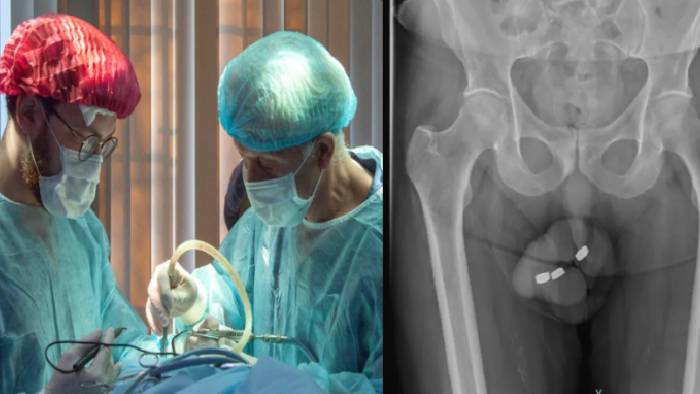

Australia: ఆస్ట్రేలియాకు చెందిన 73 ఏళ్ల వ్యక్తి విచిత్ర సమస్యను ఎదుర్కొన్నాడు. లైంగిక సంతృప్తి కోసం మూత్రనాళంలోకి చిన్న బటన్ సైజ్ బ్యాటరీలను చొప్పించుకున్నాడు. అయితే, వాటిని బటయకు తీయడంతో విఫలం కావడంతో 24 గంటల్లో సర్జరీ చేయించుకోవాల్సి వచ్చింది. ఈ విచిత్రమైన కేసు మార్చి నెలలో ‘‘యూరాలజీ కేస్ రిపోర్ట్స్’’లో ఒక అధ్యయనంలో ప్రచురించారు.

స్టడీలో 13.5 ఎంఎం వెడల్పు, 3.2 ఎంఎం ఎత్తు ఉన్న బ్యాటరీలను తొలగించడానికి వైద్యులు శస్త్రచికిత్స చేయాల్సి వచ్చింది. గతంలో కూడా సదరు వ్యక్తి లైంగిక సంతృప్తి కోసం పురుషాంగంలోని మూత్రనాళంలోకి ఇలాగే బ్యాటరీలను చొప్పించుకున్నాడు, వాటిని సులభంగానే ఎలాంటి సమస్య లేకుండా తొలగించుకున్నాడు, ఈ సారి మాత్రం కథ అడ్డం తిరిగింది. ‘పెనైల్ యురేత్రా’ సమీపంలోకి ఈ బ్యాటరీలు చేరిపోయాయి. దీంతో అతడు వాటిని తొలగించుకోలేకపోయాడు.

పరిస్థితిని తీవ్రతను గమనించిన వైద్యులు, ఆ బ్యాటరీలు రెండు గంటల్లోనే నెక్రోసిస్, శరీర కణజాలం మరణానికి కారణమవుతుండని తెలిసి సర్జరీ చేసి వాటిని తొలగించారు. అతను తీవ్రమైన ఫారఫిమోసిస్‌తో బాధపడ్డాడు, మూత్ర విసర్జన ఆగిపోయింది, సకాలంలో వైద్యం అందకపోతే కణజాలాలు నాశనమయ్యేవని వైద్యులు చెప్పారు. ఇదే కాకుండా గ్యాంగ్రీన్ అనే ప్రాణంతకమైూన ఇన్ఫెక్షన్ గురించి వైద్యులు భయపడ్డారు.

సదరు వ్యక్తి గత మూడేళ్లుగా అంగస్తంభన సమస్యతో బాధపడుతున్నాడు, షాక్ వేవ్ థెరపీని కూడా చేయించుకున్నట్లు నివేదికలో తేలింది. ప్రస్తుతం అతను డిశ్చార్జ్ అయ్యాడు, అయితే, పురుషాంగం వాపు, మూత్ర సమస్యల కారణంగా ఆస్పత్రికి తిరిగి వచ్చాడు. ప్రస్తుతం అతని పురుషాంగంలో మూత్రనాళాల నిర్మాణం కోసం మూడు సర్జరీలు చేయాల్సి ఉందని పరిశోధకులు తెలిపారు. పరిస్థితిని అంచనా వేసిన తర్వాత ఇది సరైన ఎంపిక కాదని నిర్ణయించుకున్నారు.